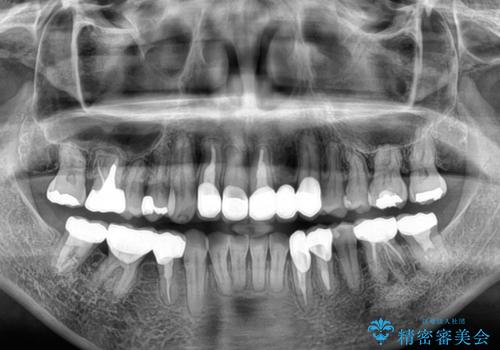

矯正治療によって前歯にスペースを作り、左右対称となるようにオールセラミッククラウンにて補綴治療を行うとしました。

他にも奥歯の咬み合わせに問題があったので、全顎的な矯正治療を行い、前歯以外にも口を開けたときに目立つ奥の銀歯をセラミッククラウンにて補綴治療を行うこととしました。

前歯の横幅が大きいことも気になっていたので、矯正治療で前歯5本の幅をコントロールしながら移動させ、治療開始前より一回りサイズの小さいセラミッククラウンを装着することができました。